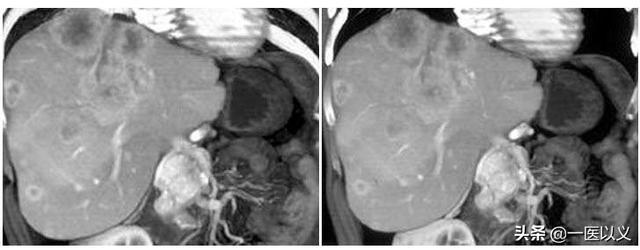

ほとんどの海綿状血管腫は、健康診断の超音波検査で偶然発見される。典型的な病変は超音波、CT、MRでより特徴的な画像を示し、定性的診断は難しくない。超音波検査およびCTの強調像では、典型的に'early out and late in'であり、MRスキャンのT2では'電球徴候'(下図)を示す。